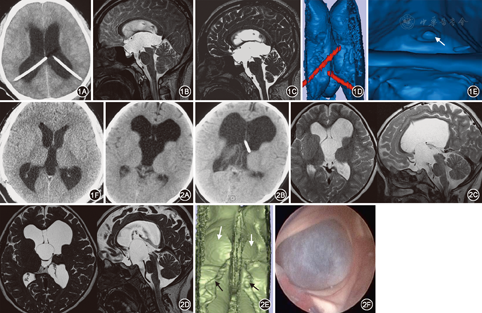

典型病例介绍:例1.患者男,24岁,因脑积水分流术后2年入院,患者2年前因脑积水在外院行VP分流术,术后短暂好转后恶化,再次于对侧行VPS,无明显好转。现患者头痛、记忆力下降、尿频,精神极差。行常规MR检查,T2矢状位疑似中脑导水管附近梗阻,3D-SPACE清晰显示中脑导水管处有薄膜梗阻。诊断:(1)梗阻性脑积水;(2)双侧脑室-腹腔分流术后。行ETV手术,术后患者症状消失,复查CT脑室变小,图1。例2.患儿女2岁,因头痛2周在外院诊断为脑积水,行脑室-腹腔分流术,术后疗效不佳,头痛缓解不明显,行磁共振3D-SPACE检查提示双侧室间孔处有薄膜堵塞,采用3D Slicer软件三维重建,虚拟内镜直视下诊断为桥前池囊肿,术中脑室镜直视下证实为桥前池囊肿,图2。